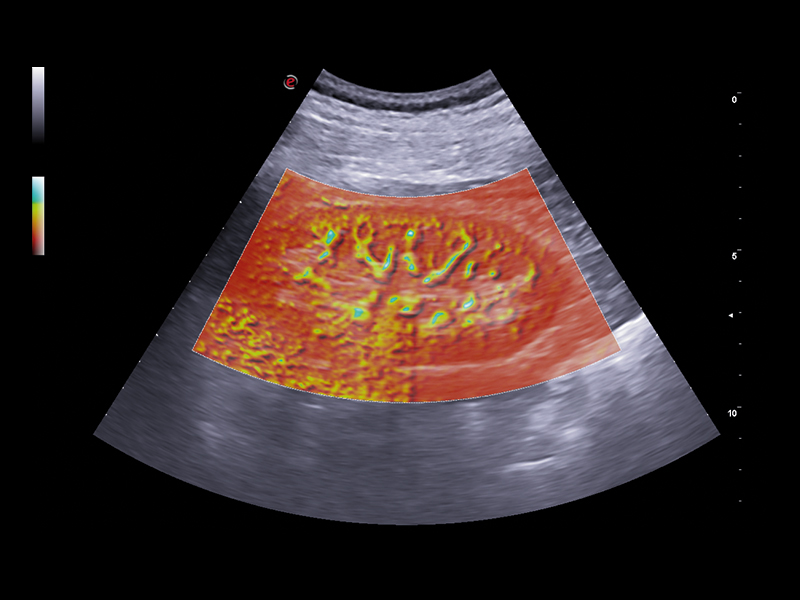

• microV: latest Esaote technology for microvascularisation visualisation with an elevated degree of sensitivity even in very small vessels and with slow flow detection. It enables advanced hemodynamic evaluation of lesions even in deep areas of the liver, thanks to exclusive filters that enhance only blood signals.